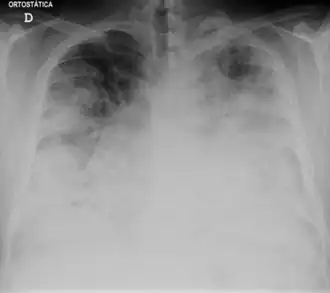

| Simptome | cefalee[1] febră[1] tuse[1] mialgie[1] frisoane[*][2] pneumonie[2] |

| Metodă de diagnostic | Hemogramă radiografia toracelui[*] tomografie computerizată[*] Cultură microbiologică Imunofluorescență ELISA reacție de polimerizare în lanț |

- Boala legionarilor, denumită și „febra legiunii”,[9] este forma mai gravă a infecției, care produce pneumonie.[10]